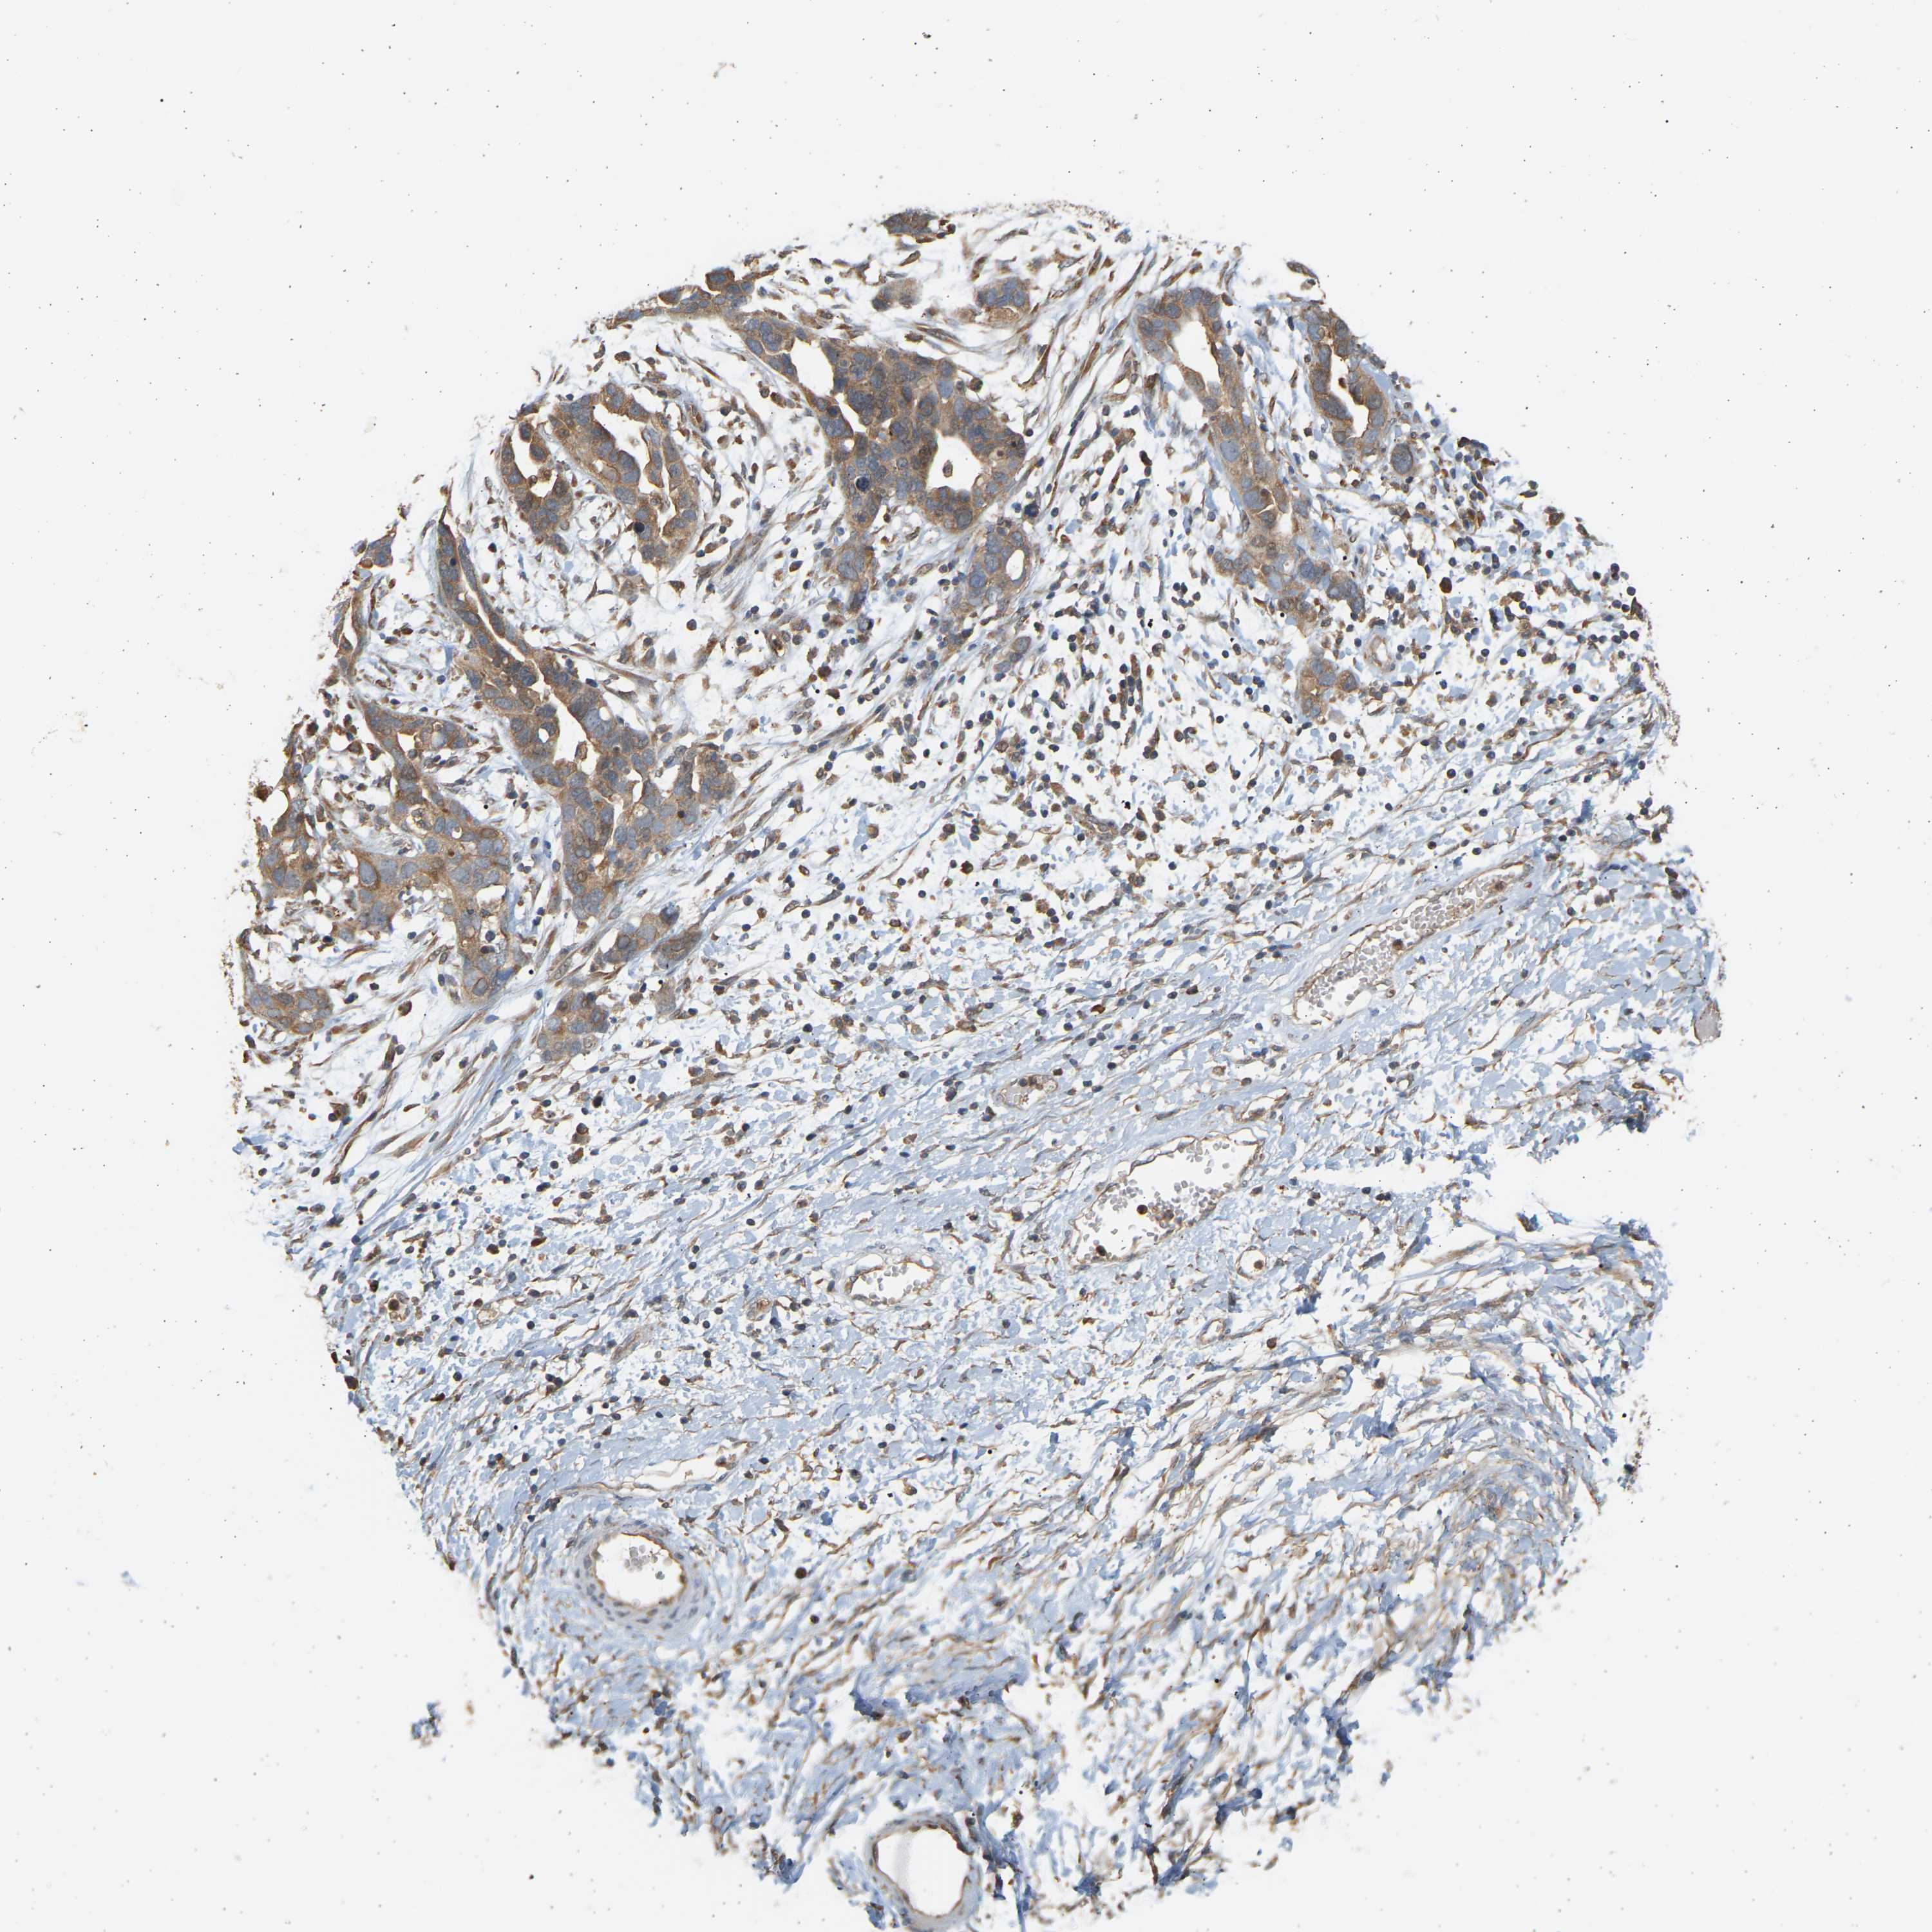

OVARIAN CANCER - Protein expressioni

A mouse-over function shows sample information and annotation data. Click on an image to view it in a full screen mode. Samples can be filtered based on level of antibody staining by selecting one or several of the following categories: high, medium, low and not detected. The assay and annotation is described here.

Note that samples used for immunohistochemistry by the Human Protein Atlas do not correspond to samples in the TCGA dataset.

Antibody stainingi

Antibody staining in the annotated cell types in the current human tissue is reported as not detected, low, medium, or high, based on conventional immunohistochemistry profiling in selected tissues. This score is based on the combination of the staining intensity and fraction of stained cells.

Each image is clickable and will lead to virtual microscopy that enables deeper exploration of all samples and also displays staining intensity scores, fraction scores and subcellular localization as well as patient and tissue information for each sample.

Antibody HPA058284

Antibody CAB020701

Staining

High

Medium

Low

Not detected

Intensity

Strong

Moderate

Weak

Negative

Quantity

>75%

75%-25%

<25%

None

Location

Nuclear

Cytoplasmic/membranous

Cytoplasmic/membranous,nuclear

Cystadenocarcinoma, serous, NOS

Cystadenocarcinoma, mucinous, NOS

Carcinoma, endometroid